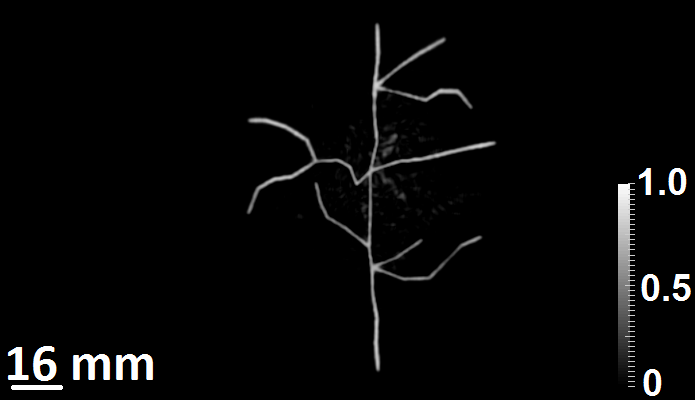

The initial pressure distribution assumed in the simulation studies mimicked cortical blood vessels (CBVs). The phantom, shown in Fig. 4, consisted of CBVs positioned approximately 6 mm6 mm6\text{ mm} below the inner surface of the skull. The 2D maximum intensity projection images along the x-,y- and z-axis of the initial pressure distribution are shown in Fig. 4.

Refer to caption

(a)

(b)

(c)

Figure 4: The maximum intensity projection of the initial pressure distribution (a) along the z-axis, (b) along the y-axis, and (c) along the x-axis.